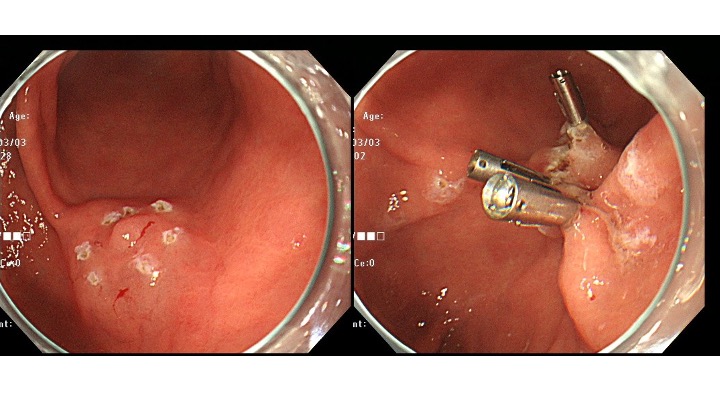

治療日の拡大内視鏡所見です。

通常観察はやや白色調の隆起、NBI観察では、癌の特徴である色差(癌:茶色、周辺:緑色)を認めています。

(1)癌の血管は、視認できず。

(2)表面構造に、癌を示唆する所見も視認できず。

処置時間は8分で終了しています。